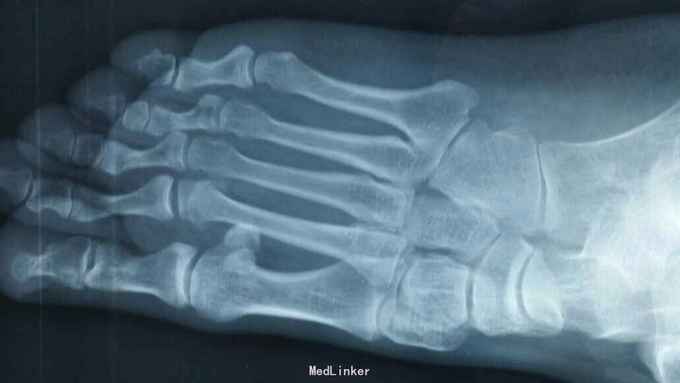

主诉:右足外伤后肿痛,活动受限11天。 现病史:患者于2015年11月10日摔伤右足,当即肿痛,活动受限,急去当地医院拍片及入院行石膏固定保守治疗,效果不佳,为求进一步治疗来诊我院,经门诊阅片及查体后以“右足多发骨折,脱位,韧带损伤”为诊断收入院。

查体:右足略肿胀,畸形明显,足背压痛广泛阳性,可触及骨擦音及骨察感,活动受限,末梢各趾活动自如,足背动脉清。 辅助检查:大致正常。

诊断:右足多发骨折伴跖跗关节脱位,韧带损伤 治疗:患者入院后,完善检查,于2015年11月25日行手术治疗,现切口愈合良好。